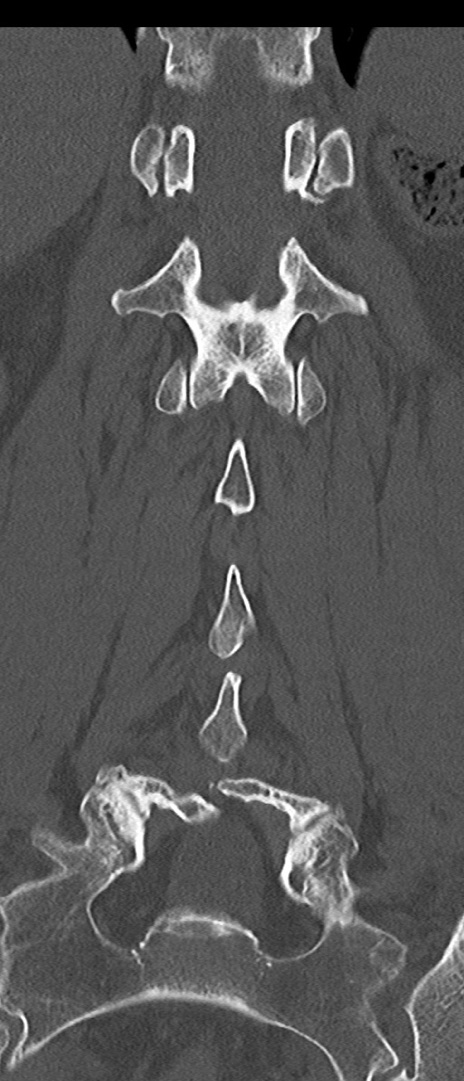

【整形】TIPS症例4 腰椎CT(冠状断像)

腰椎CT